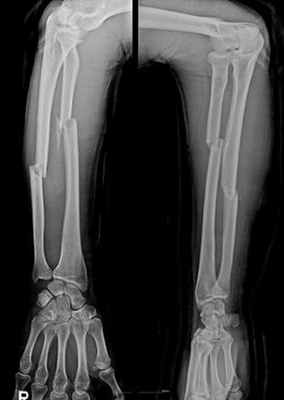

Переломы костей предплечья могут быть изолированными, а могут и сочетаться с другими повреждениями. Переломы костей предплечья чаще встречаются со смещением отломков, реже без смещения. В зависимости от уровня перелома различают — повреждение проксимального отдела, повреждение диафиза, повреждение дистального отдела предплечья. Переломы костей предплечья могут быт закрытыми — встречаются чаще, и открытыми — более реже.

При диафизарном переломе локтевой и лучевой кости, не осложненной смещением, предплечье фиксируют в положении сгиба с захватом лучезапястного и локтевого суставов сроком на пять недель. При переломе со смещением выполняют репозицию (восстановление правильного положения смещенных отломков кости) и накладывают гипсовую повязку сроком до шести недель.

При диафизарном переломе обеих костей предплечья без смещения на руку, согнутую в локте, накладывают лонгет, захватывая лучезапястный и локтевой сустав сроком до восьми недель. При смещении отломков проводят репозицию или остеосинтез в зависимости от тяжести повреждения. После оперативного вмешательства накладывают гипсовую повязку сроком до трех месяцев.

Переломы диафизарного отдела костей предплечья